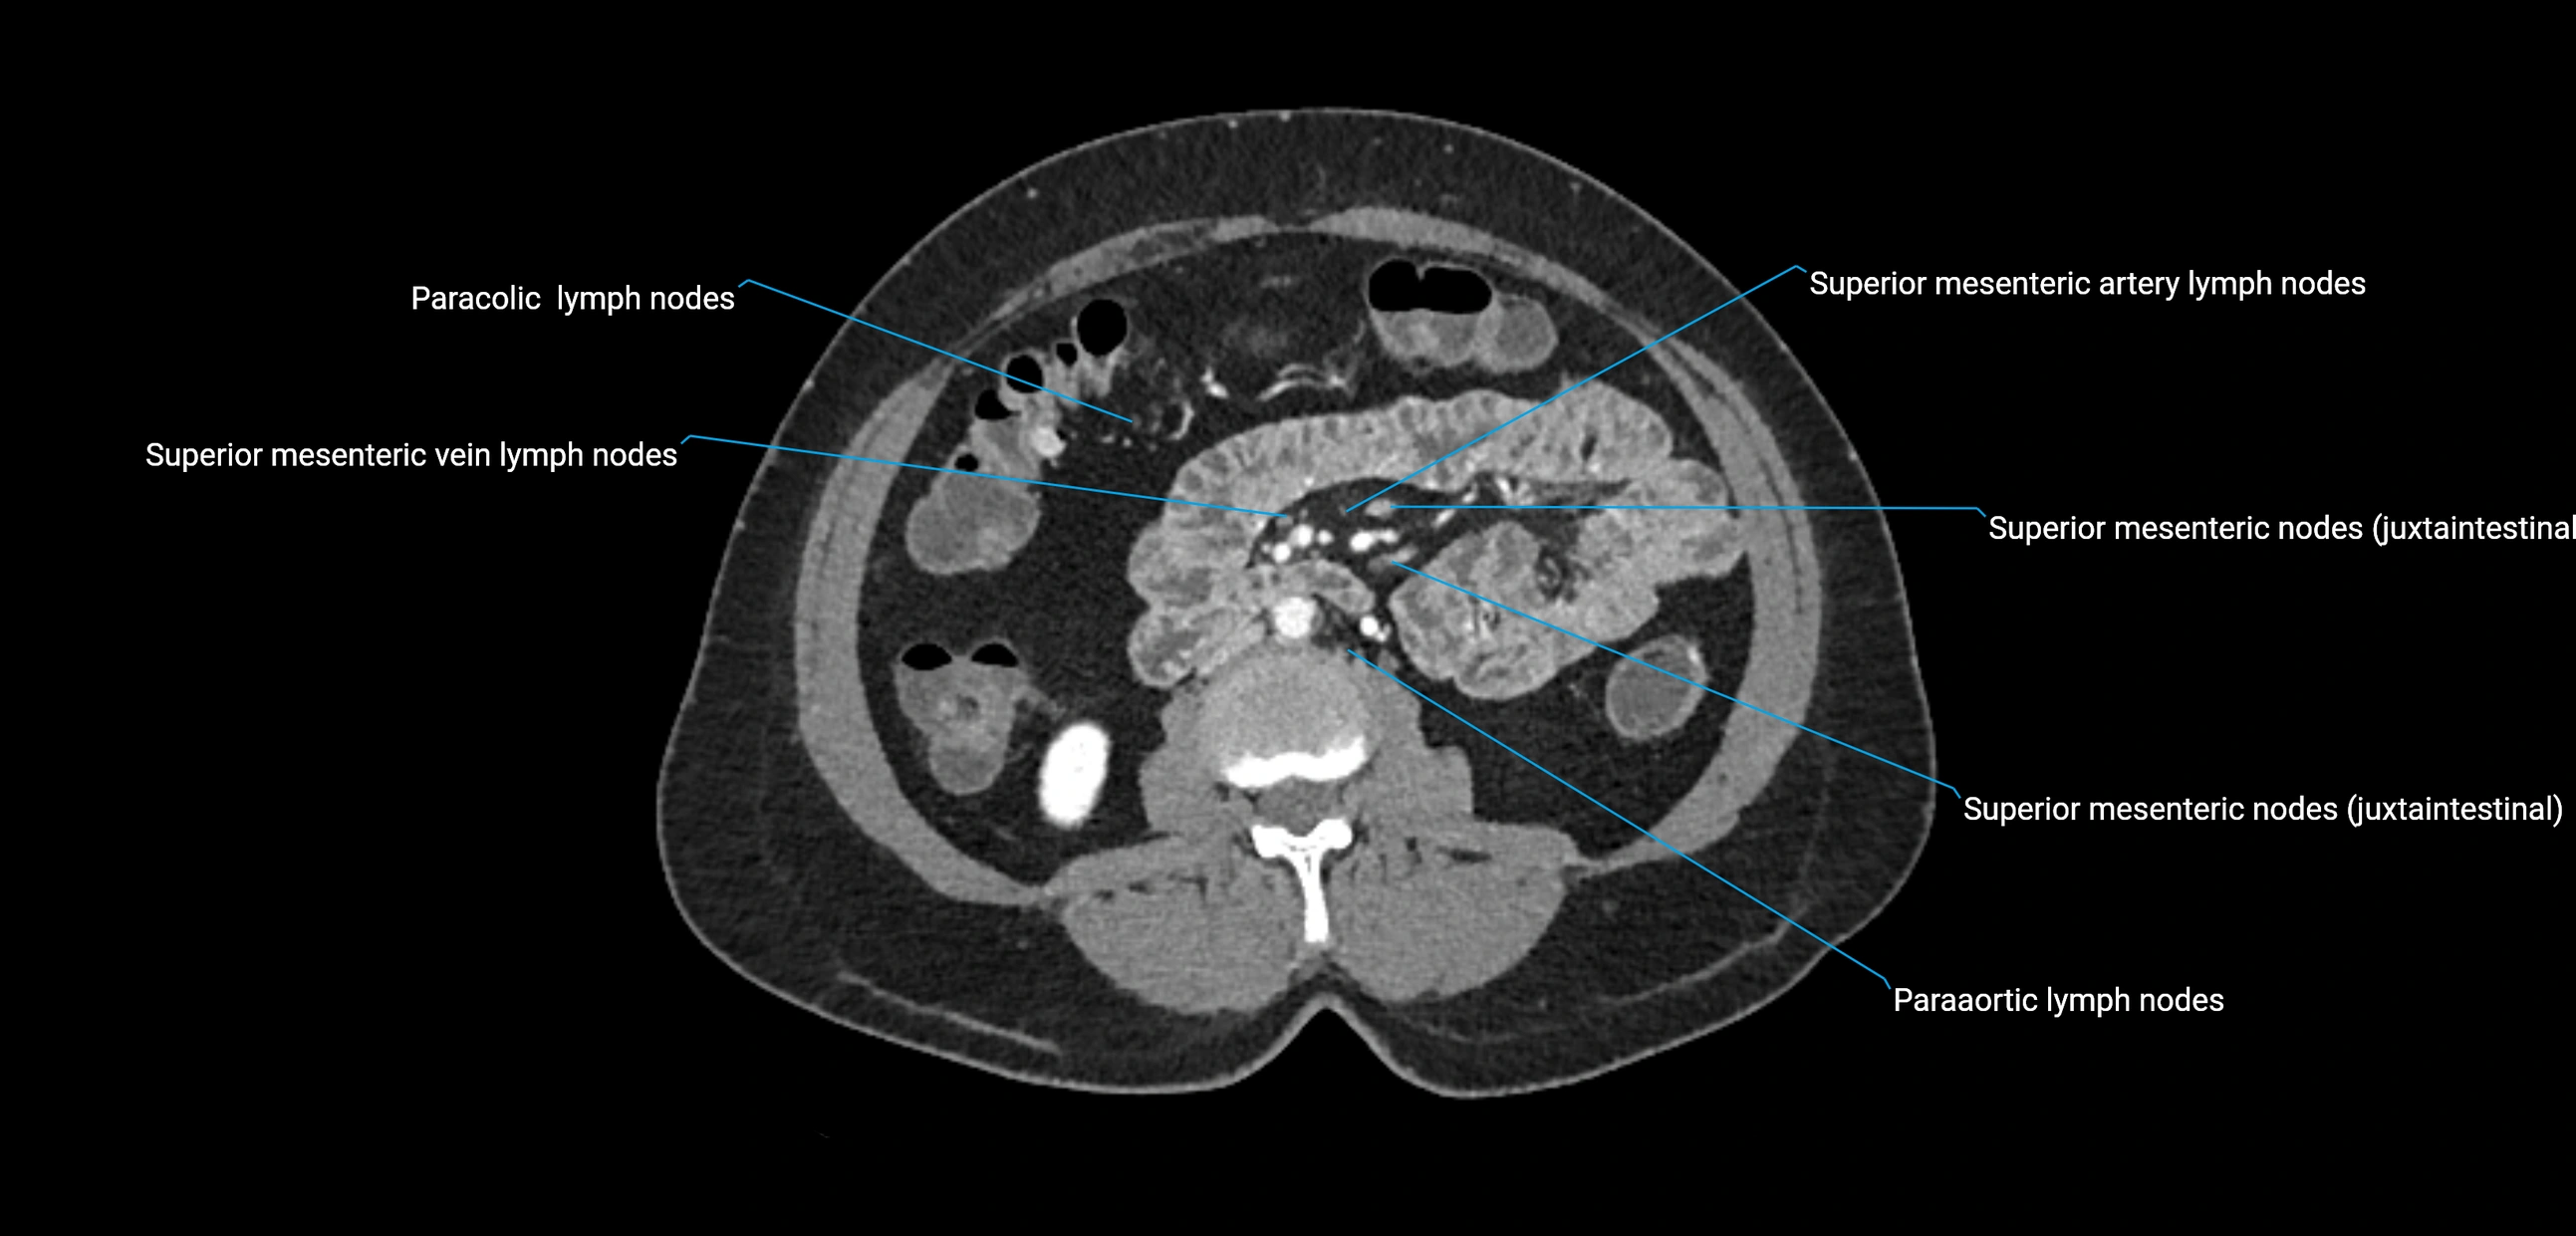

CT image

image